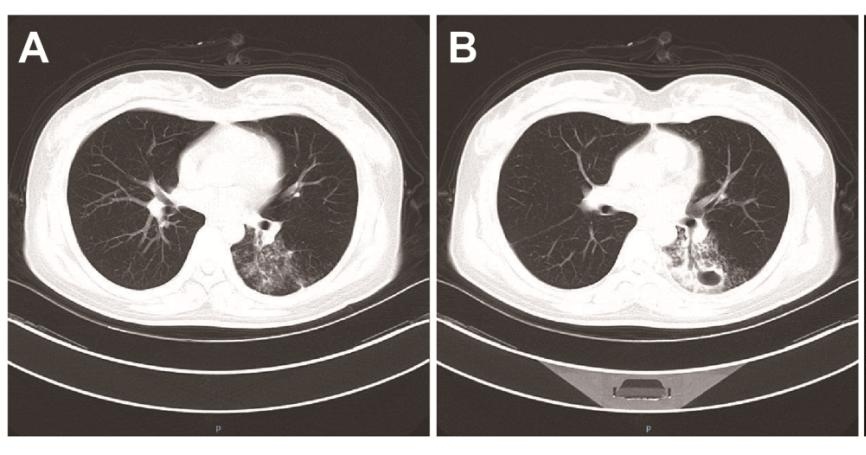

小宁胸部CT检查提示:左下肺实变并空洞,考虑感染或吸入性肺炎。结合血沉升高,小宁考虑是肺结核,排除新冠肺炎。

鉴别第二点是根据她的CT表现,是空洞型肺结核典型表现,特点是空洞内壁光滑,周围有很多形态的卫星灶,表现为粟粒状小斑点,还有一些小树芽和小斑片影,就像地球周围环绕了很多卫星。